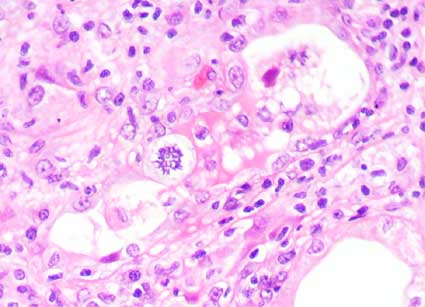

Figura 4.

H&E, X400.